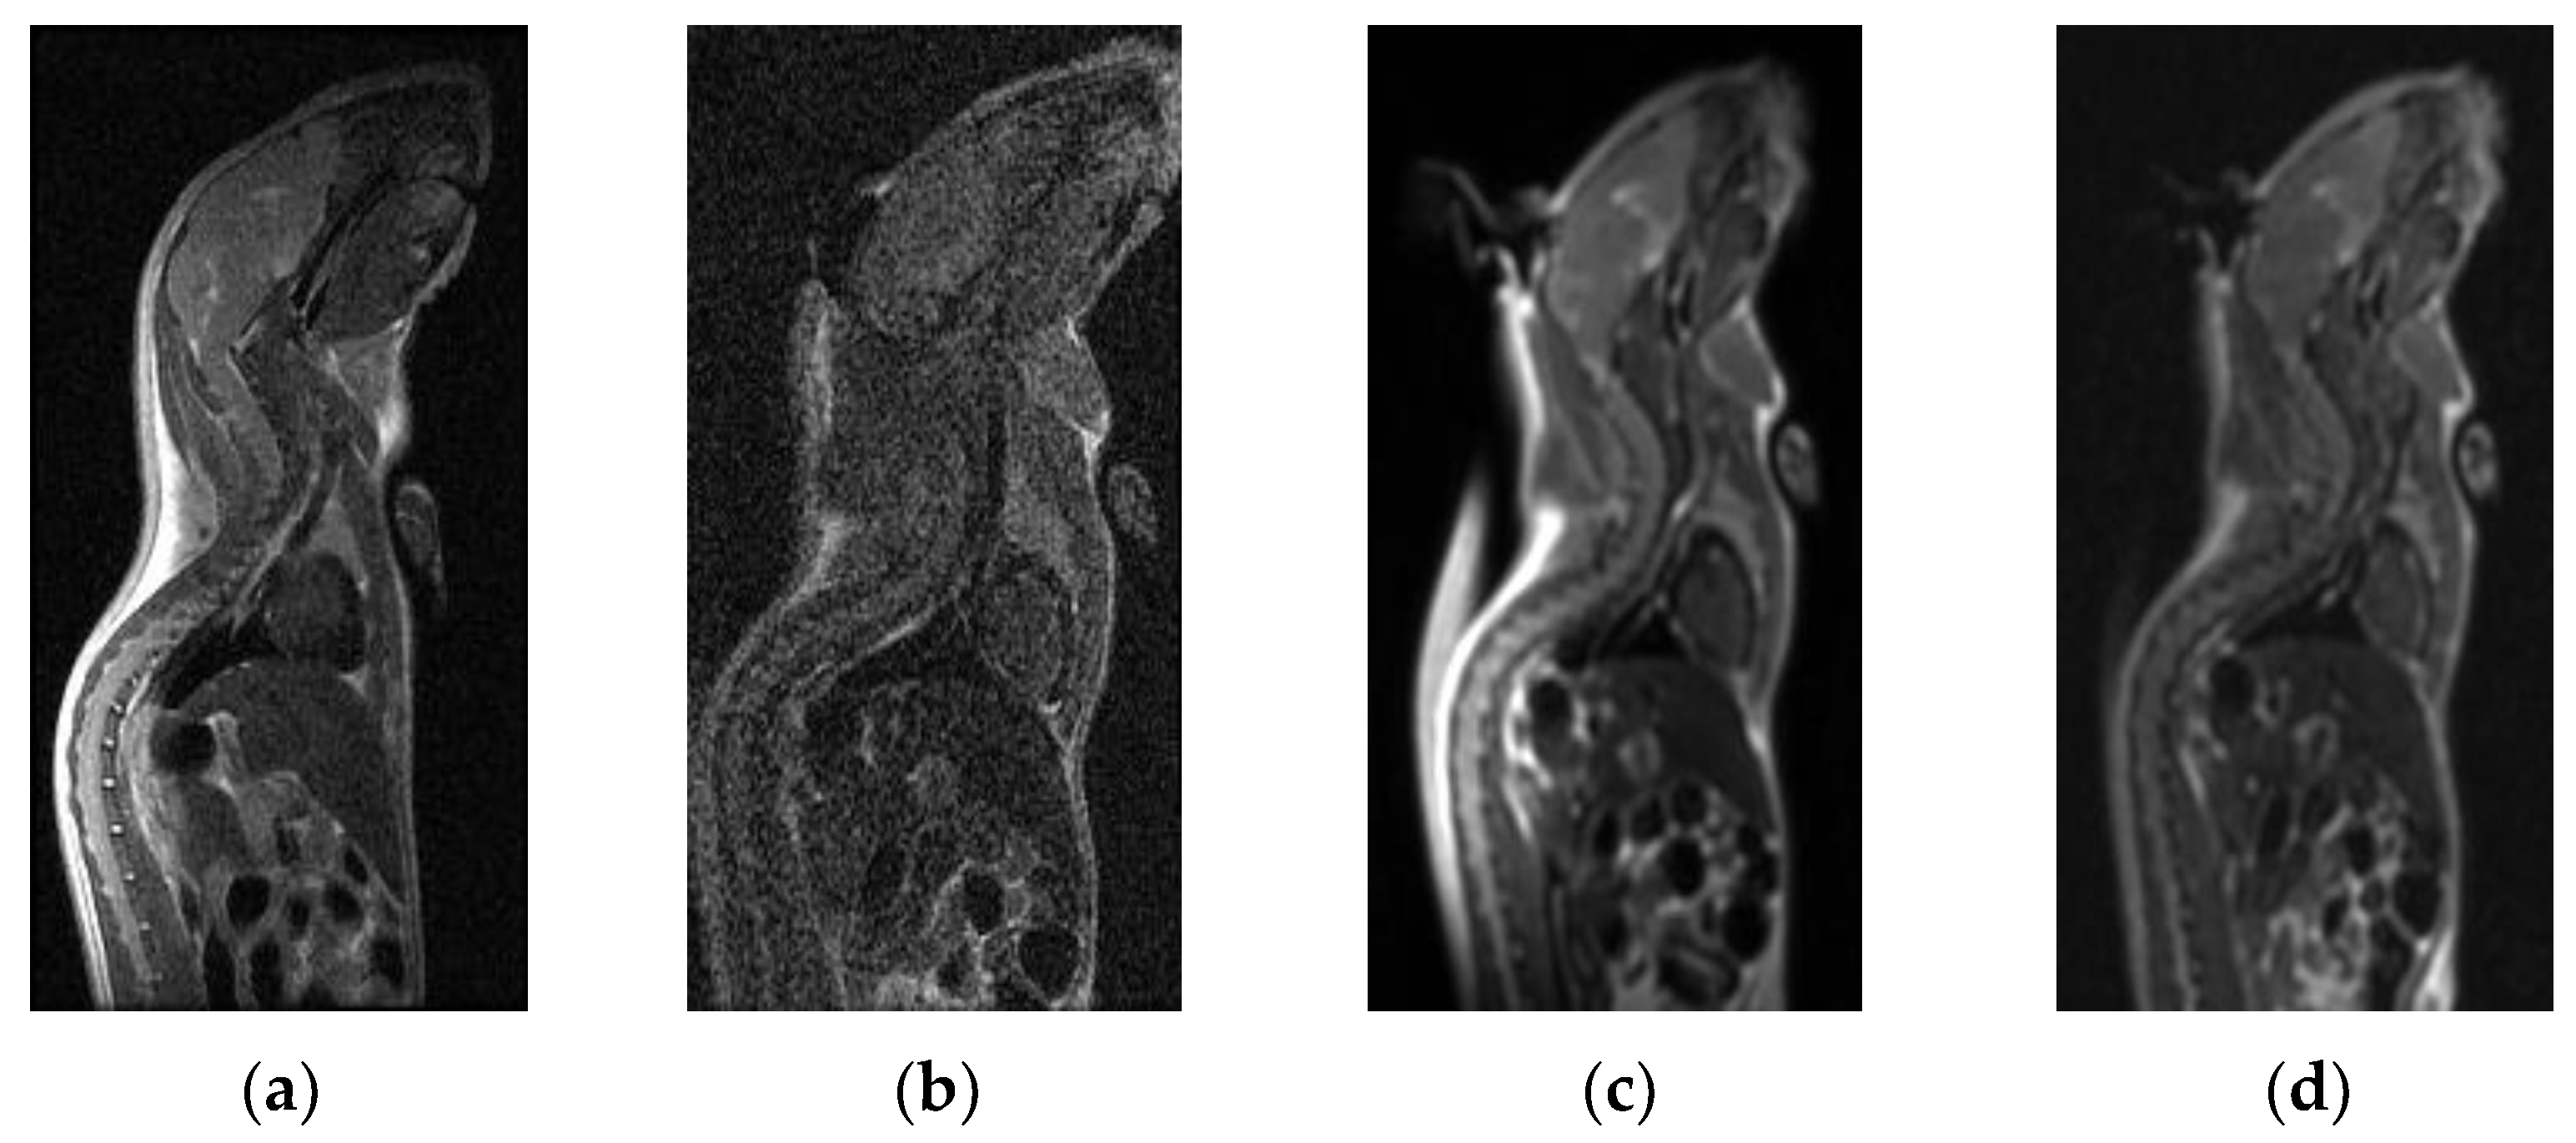

| 2D-FSE T2WI sag body | 4.75 ± 0.45 | 2.92 ± 0.29 | −3.169 | 0.002 |

| The 3D-CUBE sag body | 4.46 ± 0.50 | 3.17 ± 0.39 | −2.859 | 0.004 |